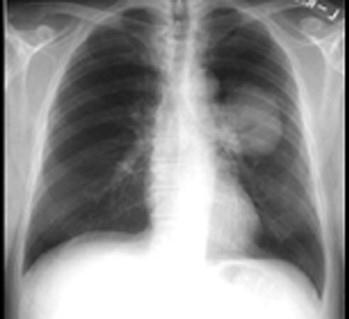

问题 既往健康的68岁男性患者,吸烟40年,因咳嗽,反复肺部感染,于门诊抗炎治疗近1年,胸部X线复查如图所示,形态不规则,边缘不整齐,收入院进 一步检查治疗。 根据其病史,体检,X线表现,该患者肺癌的病理类型可能是 ( )

选项 A、大细胞癌 B、混合性癌 C、小细胞癌 D、腺癌 E、鳞状细胞癌

答案 E